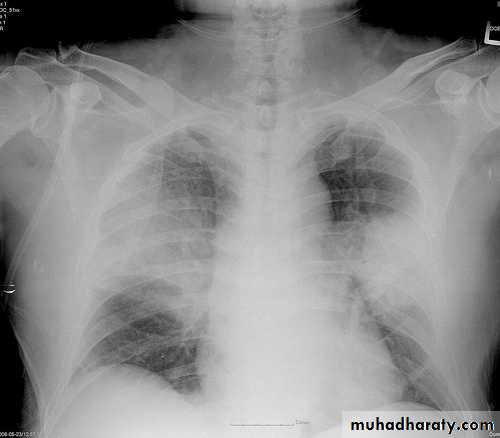

Lobar pneumonia: homogenous consolidation of one or more lung lobes, often with associated pleural effusion

Streptococcus pneumoniae is the most common cause, characteristically has rapid onset, with high fever, pleuritic pain, rusty sputum, herpes labialis and lobar consolidation on chest X-ray.

Multiple lobe involvement, cavitation, pneumatocoele and abscess formation are characteristic.

A chest X-ray is usually sufficient to confirm the clinical diagnosis of pneumonia.

In lobar pneumonia, a homogenous opacity localized to the affected lobe or segment usually appears within 12 – 18 hours of the onset of illness.

Chest X-ray helps in:• Differentiating CAP from other diagnosis

• Provide information about severity (cavitation and multilobar involvement)

• Detects complications (pleural effusion or abscess formation).

• It can occasionally suggest an aetiological agent (pneumatocoele in Staphylococcus aureus pneumonia).